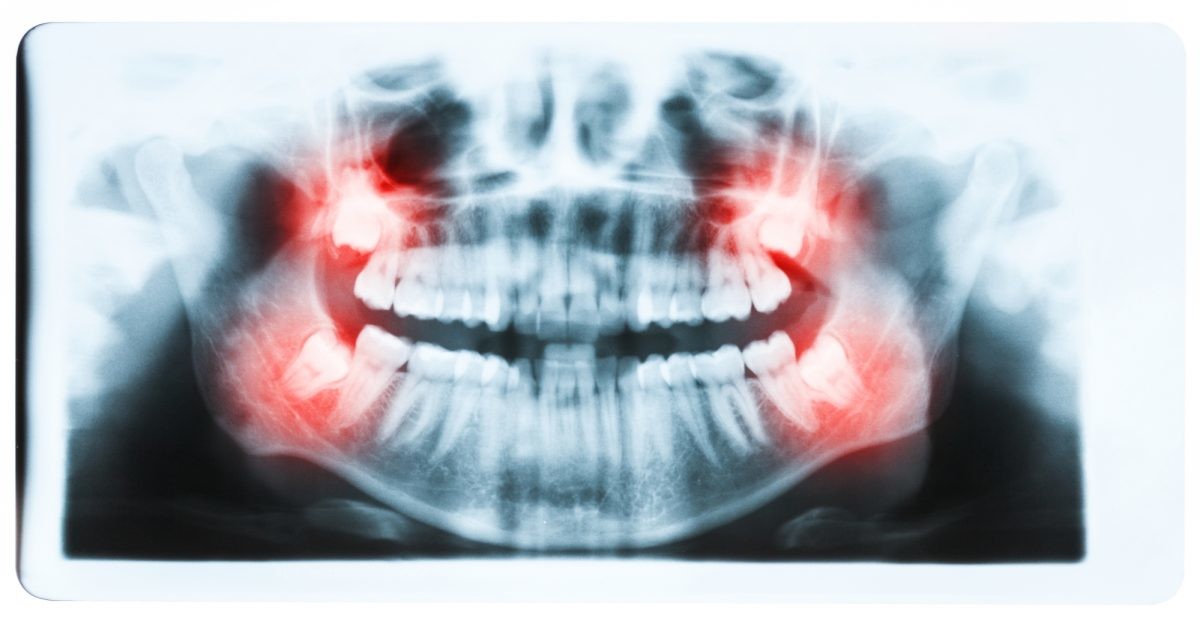

Do Wisdom teeth affect braces?

For those people who have wisdom teeth, they usually erupt in early adulthood. Wisdom teeth may cause dental issues like overcrowding, especially if they’re impacted. However, many people have plenty of room for their wisdom teeth and they have no problems with them.

During this age frame, many people also get braces or just have them removed. People are often concerned that the eruption of their wisdom teeth will affect the progress they’ve made with braces.

Like previously stated, many people have their wisdom teeth come in with no problems. The teeth grow in straight and don’t affect the person’s bite. So overall, no, wisdom teeth do not cause significant overcrowding in the front of the mouth or severely disrupt any progress that was made with dental work like braces.

However, if they do not come in correctly or if a person’s jaw simply doesn’t have room for the new teeth, they can cause overcrowding among the back teeth.

It’s important to note that wisdom teeth are not the sole reason a person’s teeth begin to move. It’s been confirmed that people’s teeth move over time with or without the help of wisdom teeth. Additionally, when people have their braces removed, they may neglect to wear their retainers. Without the use of the retainer, a person’s teeth may begin to shift again.

While wisdom teeth may not necessarily cause a major issue with the dental progress that has been made with braces, there may still be reasons to have a wisdom tooth extraction. There are many wisdom tooth concerns that may call for tooth removal surgery, including: Crowding of back teeth, Infected gums, Bone defects, Root resorption, Dental diseases.

If a wisdom tooth becomes impacted or doesn’t erupt straight up, this can cause significant problems for the person. While some people may experience absolutely no problems with their wisdom teeth or get lucky enough to not have any of these extra molars at all, others may experience problems with them.

Fortunately, impacted tooth removal is a common procedure and can provide relief from any pain and discomfort caused by these teeth. In fact, wisdom teeth removal is more common than dental implant procedures, which about three million people have every year.

It’s important to remember that it’s perfectly normal for your teeth to move as you age. If your wisdom teeth are beginning to come in and are causing you pain and discomfort, your dentist may refer you to an experienced oral surgeon to discuss having them removed.